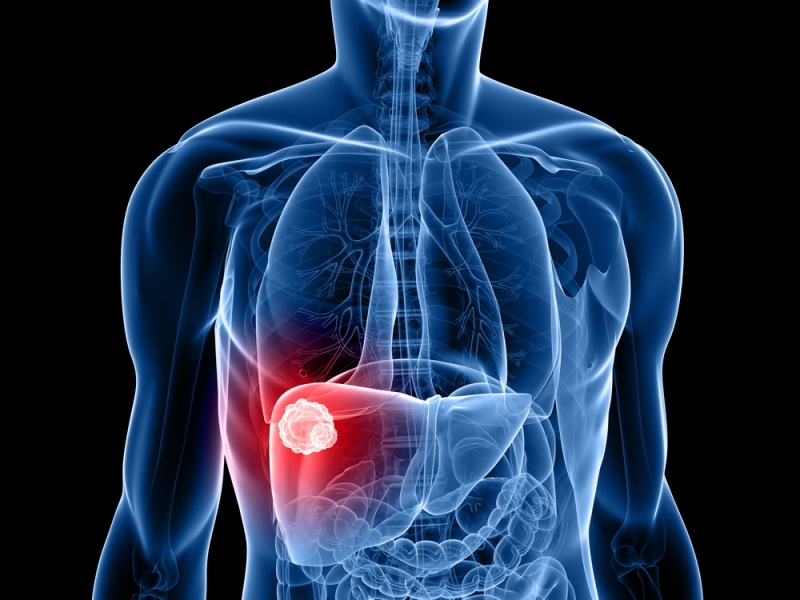

Liver cancer is one of the deadliest and more common forms of cancer. In Britain, about one in 100 men and one in 200 women develop liver cancer at some point in their lives. To minimize risks, the WCRF recommends that women consume no more than one drink a day and men consume two or less.